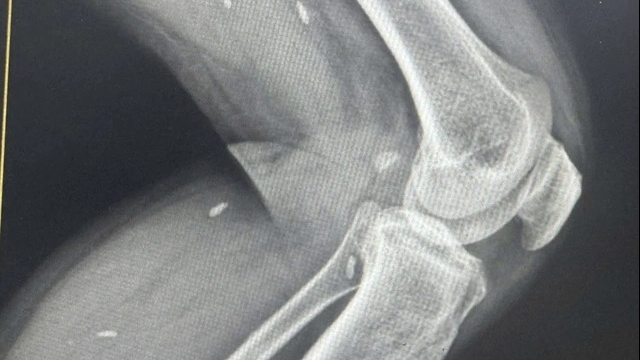

Hơn một năm trước, vào ngày 2/8/2021, trong quá trình lao động, ông B (ở xã Đạo Đức, huyện Bình Xuyên) không may bị máy cưa cắt đứt lìa 1/3 dưới đùi bên phải. Ngay sau đó 30 phút, người bệnh đã được đưa đến Bệnh viện đa khoa tỉnh Vĩnh Phúc cùng với chiếc chân bên phải bị cắt lìa bảo quản trong thùng đá.

Các bác sĩ bệnh viện đã chạy đua với thời gian, khẩn trương cấp cứu, hồi sức cho người bệnh. Trải qua 3,5 giờ phẫu thuật, chân phải của người bệnh đã được nối lại thành công.